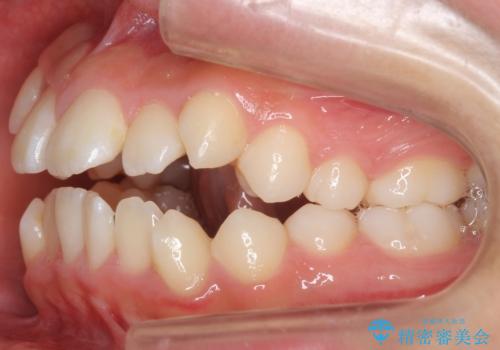

インビザラインチェンジで成功 インビザラインで八重歯の抜歯矯正

- かみ合わせを主訴に来院。

八重歯や、前歯のオープンバイト(開咬)の症状があり、マウスピース(インビザライン)矯正単独では治すのが難しい症状が複合していました。

八重歯や抜歯したスペースの閉鎖をワイヤー矯正で前半行い、治療後半は目立たないインビザラインでかみ合わせを調整しました。